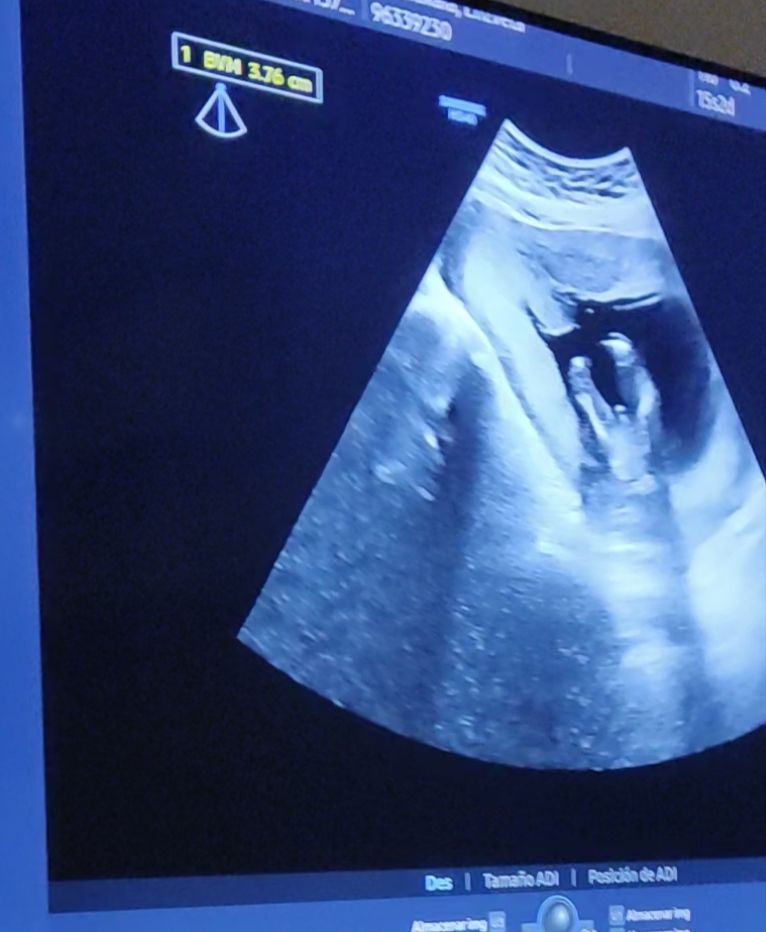

Пол в 15 недель 2 дня, мальчик?

Врач сказала , что пол увидела и написала на бумажке для тортика. В итоге узнали, что у нас мальчик (на первом скриннинге тоже уж больно был половой бугорок похож на мальчишечий - фото с первого УЗИ тоже прикрепляю)

Но вот смотрела я видео и фото с 15 недель и так и не поняла - это оно или не оно (кадры будто сверху, а не снизу) и не могла же врач ошибиться на таком сроке и уверенно так записать для гендер пати мальчика😂 Дочку до второго скриннинга не видели (пряталась)

У вас УЗИ похоже на мое с сыном, думаю, у вас не ошиблись

Я ходила на скрининг, было 13 недель и 2 дня, повернули точно так же , и мальчика наверно ни с чем не спутаешь. Тут она говорит даже пол видно уже , говорить? Я говорю да,она у вас мальчик😄🥰 так что думаю, что мальчик на фото